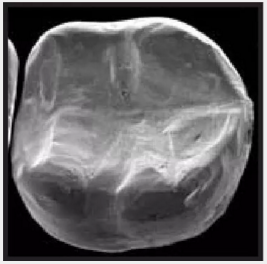

復(fù)合樹脂在即刻充填后,觀察其在電子顯微鏡下的掃描圖像,本次研究選擇了9種具有代表性的復(fù)合樹脂材料。

2.png

IPS Empress Direct Ivoclar Vivadent義獲嘉維瓦登特